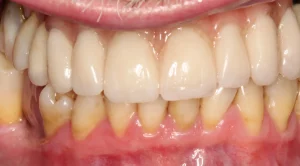

This patient was fed up with her denture and remaining loose upper teeth.

5 upper implants have been placed that support a bridge with 13 teeth in the top jaw.

This is a full arch porcelain bridge which the lady was delighted with.